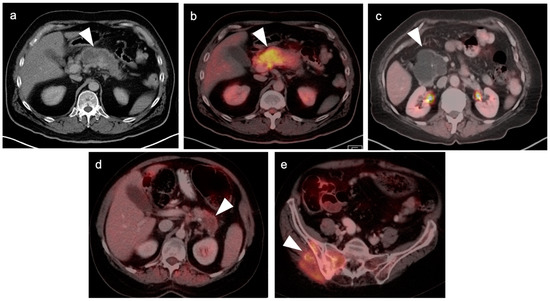

4. Hepatocellular Carcinoma

5. Cholangiocarcinoma

6. Gallbladder Carcinoma

7. Adrenal Cancer

8. Pancreatic Carcinoma